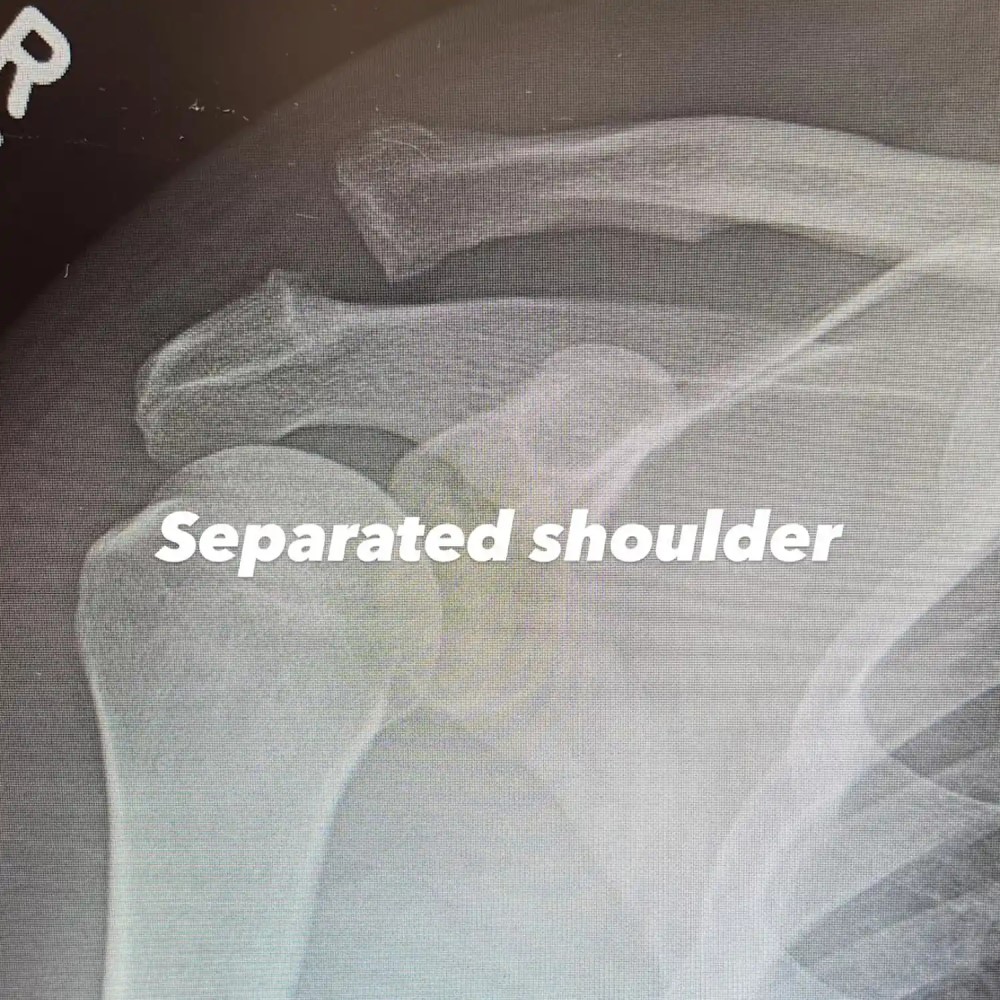

Ченнинг Татум перенес серьезную операцию на плече. 45-летний актер уже опубликовал фото с больницы. Заодно звезда танцевальных франшиз «Шаг вперед» и «Супер Майк» поделился рентгеновскими снимками руки.

Ченнинг Татум опубликовал в соцсетях рентгеновские снимки до и после операции. На рентгене после операции виден винт, который скрепляет кости. Также выложил снимок, на котором он лежит в больничной шапочке и халате. Актер не стал уточнять, при каких обстоятельствах получил травму. Известно лишь то, что он вывихнул плечо. В комментарии к посту Татум написал: